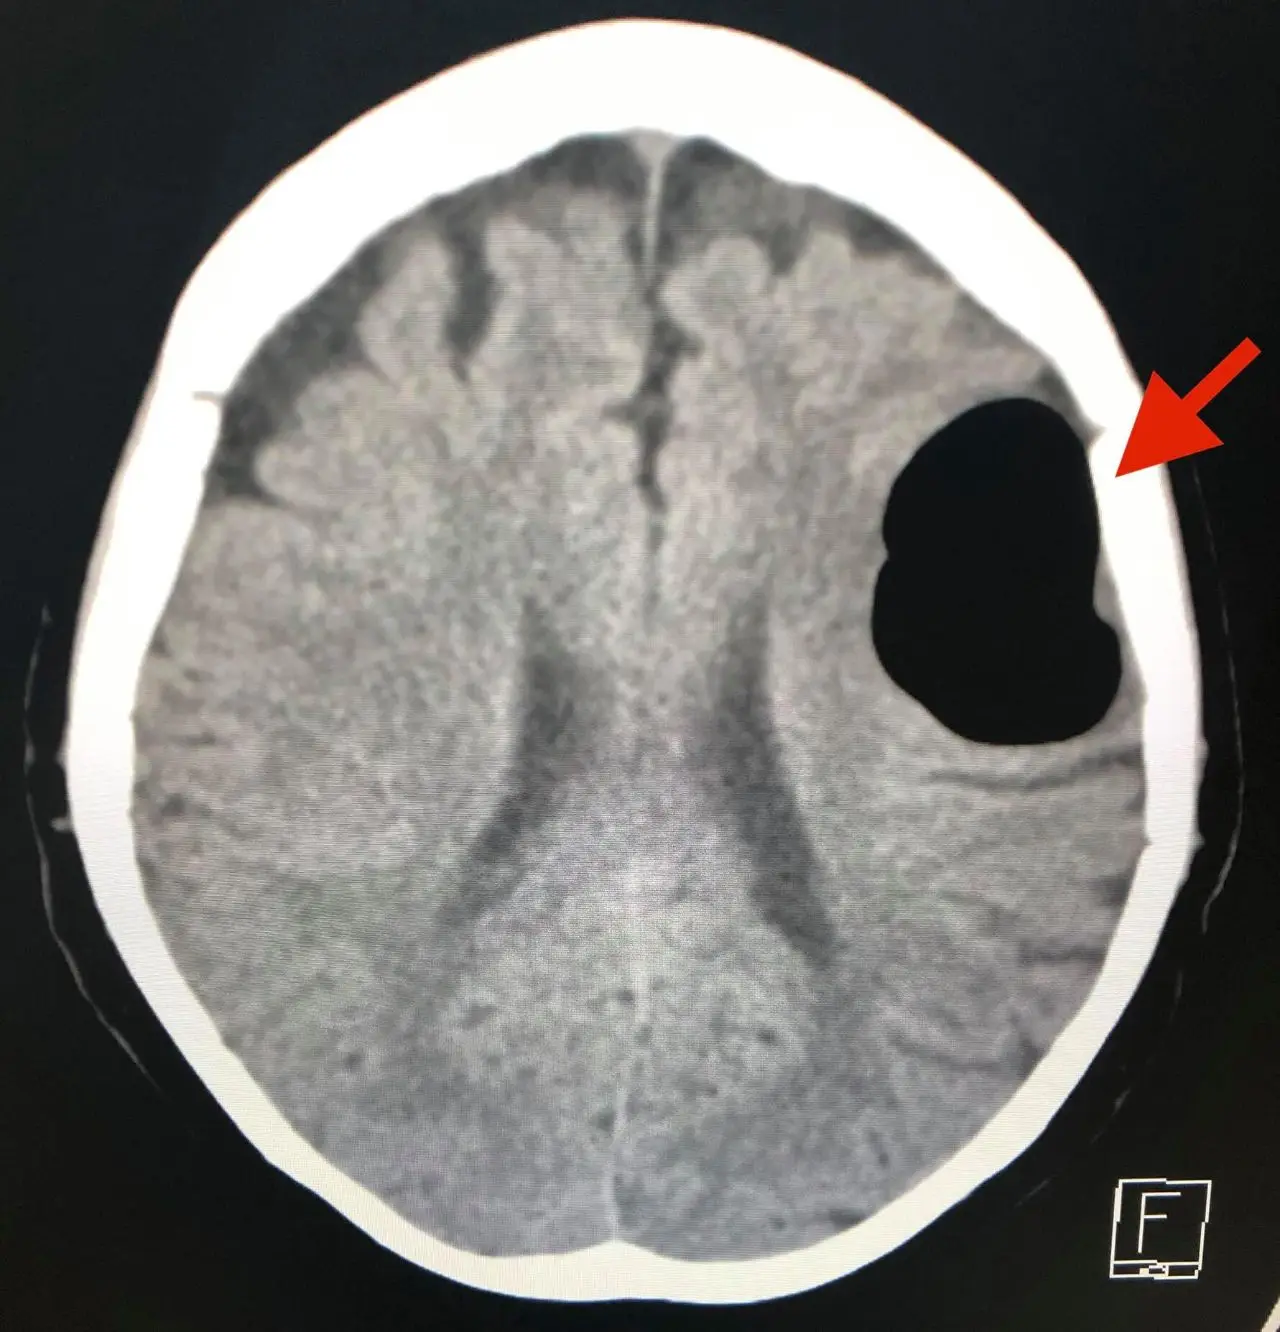

วันที่ 14 พฤษภาคม 2563 ผู้ป่วยกลับมารพ.อีกครั้งหลังจากจามแล้วเอามือปิดปากปิดจมูกเพราะไม่อยากให้มีเสียงดัง หลังทำมีอาการพูดไม่ชัด หน้าข้างขวาเบี้ยว หูข้างซ้ายอื้อ มีเสียงดัง ทำคอมพิวเตอร์สมองพบลม (air pocket) ในเนื้อสมองข้างซ้ายขนาด 5.1 × 4.1 × 2.8 เซนติเมตร (ดูรูป) ตำแหน่งเดิมเหมือนเมื่อ 3 ปี 5 เดือนก่อน แต่ปริมาตรของลมในเนื้อสมองครั้งนี้น้อยกว่า ผู้ป่วยนอนในโรงพยาบาล 4 วัน อาการดีขึ้นช้าๆ กลับบ้านได้